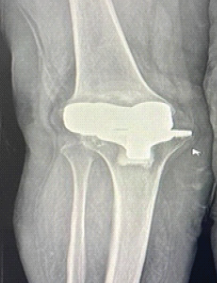

A Hybrid Surgical Approach to Late Posterolateral Instability Following Total Knee Arthroplasty: A Case Report of Posterolateral Corner Reconstruction with Component Retention

Vaibhav Bagaria , Anjali Tiwari , Shobit Deshmukh

………………………………p.202-207